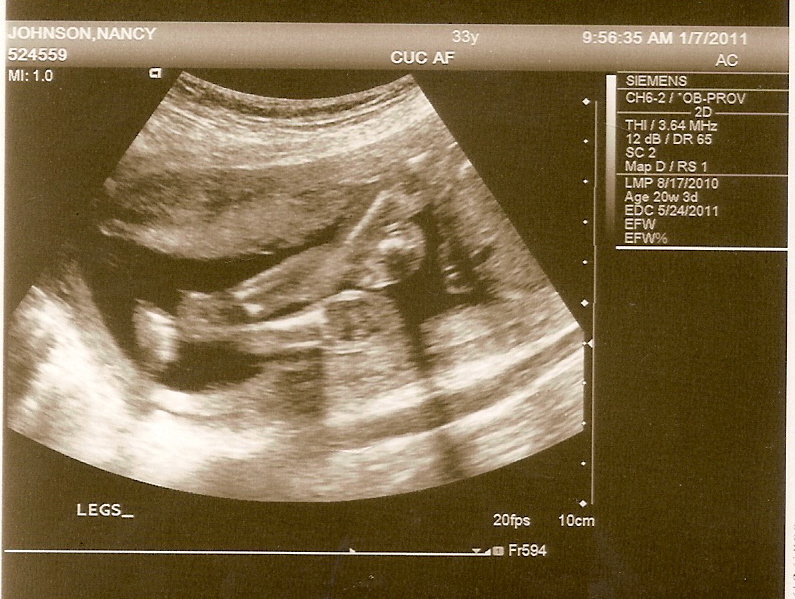

We found out that Baby #4 is going to be a boy. "Told ya!" Keira said at the ultrasound. We all thought it was going to be a boy, so we have a family of experts now. "Mom, I like your baby," Kai whispered in my ear while I was lying on the table. Keira cried b/c she thought we would get to take the baby home today. He's due May 24th. His name MIGHT be Kahanu, but we're not sure yet. Here he is...

The ultrasound tech got a good shot of what gender baby is. She said he's not shy 'cause his legs were wide open (he's a Johnson, alright!)

Those are his little knees at the right, the thigh of his leg coming up from the bottom right, and his little toes and feet at the left. Amazing that we were all less than a pound and 10" long at one time, isn't it?